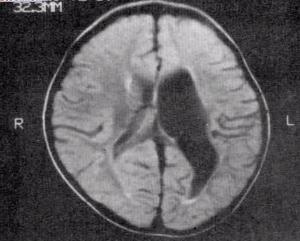

白質異常的相關疾病非常多,已知的疾病包括多發性硬化症、腦性麻痹、亞歷山大症,其他仍在研究的則有閱讀障礙、音痴、精神分裂症、注意力不足過動症、躁鬱症、語言障礙、自閉症等,其也與因老化、阿茲海默症、甚至罹患病態性說謊而認知衰退的患者有關。